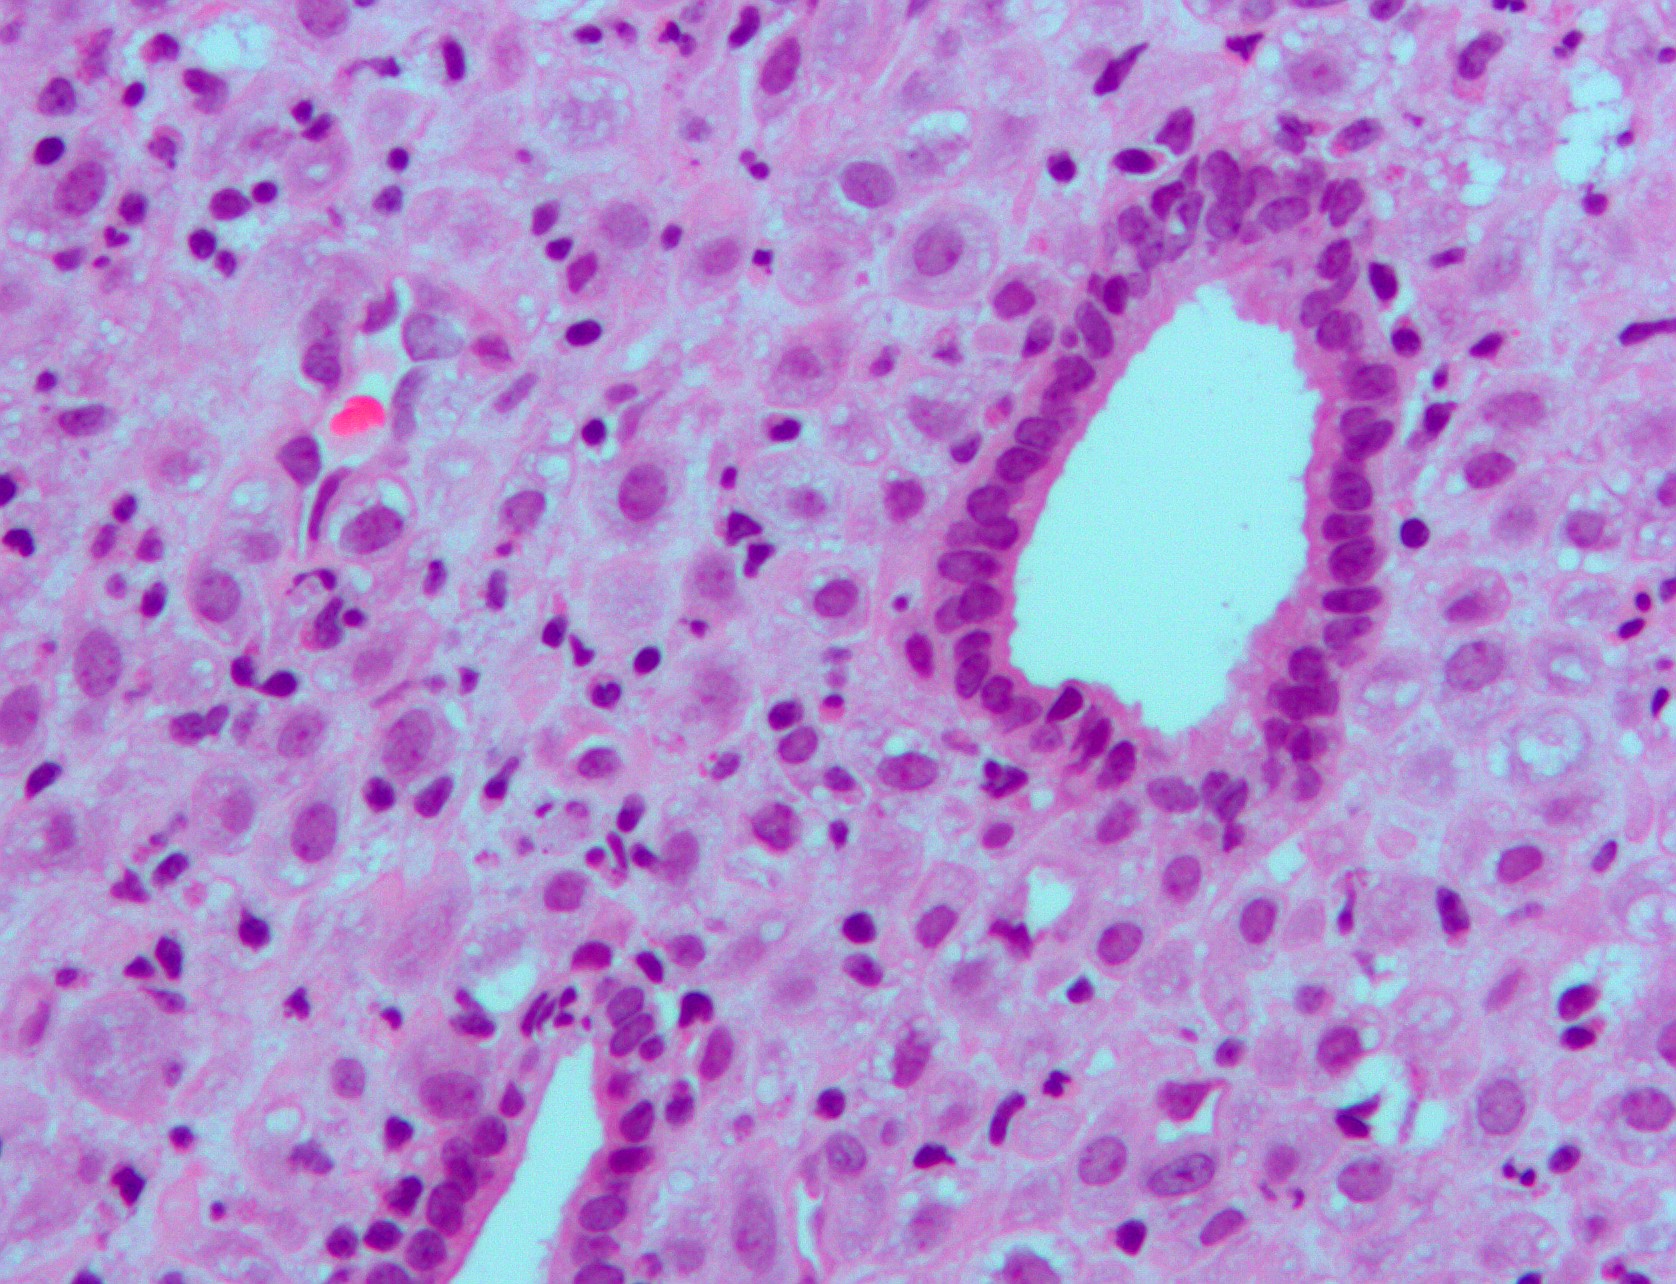

L'analisi sulle cellule endometriali in vitro ha dimostrato che i PFAS interferiscono vistosamente sulla regolazione dei geni espressi a livello dell'endometrio; su più di 20.000 geni analizzati, il progesterone normalmente ne attiva quasi 300, ma la ricerca ha riscontrato che in presenza di PFAS ne vengono alterati 127, tra cui quelli che preparano l'utero all'attecchimento dell'embrione e quindi alla fertilità.

Immagine di copertina: endometrio (Autore: Nephron - Fonte: Wikipedia)